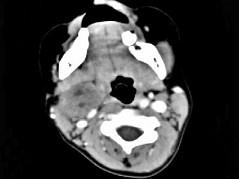

问题 女,4岁,右侧颈部可扪及一包块约两个月,无热无痛,CT如图所示,最可能的诊断为 ( )

选项 A、咽旁神经纤维瘤 B、咽旁小唾液腺混合瘤 C、咽旁副神经节瘤 D、咽旁脓肿 E、咽旁血管外皮瘤

答案 A